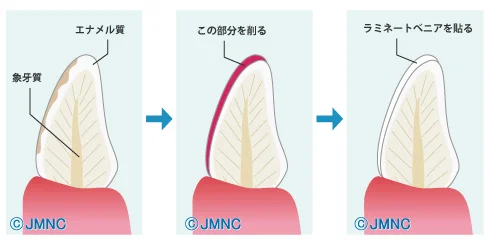

そもそもラミネートべニアとは。

こんな感じで、歯の表面をすんごい微妙に削り、うすーいセラミックを貼り付けるという治療になります。

歯の変色が強い場合で、それが人工物ではなく天然の、ご自身の歯の場合に使用するものです。

歯の色は綺麗にしたいけどセラミックとかで大きく歯を削りたくはない・・・。

そんな時に選択する治療法です。